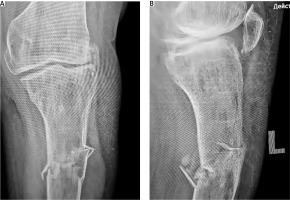

A 52-year-old female patient sustained a low-energy injury as a result of a fall from her own height, impacting the left lower limb. In the emergency department, the patient was assessed by an orthopedic specialist. Diagnostic evaluation included radiographic imaging to confirm the fracture and standard laboratory blood tests to evaluate general clinical parameters, performed in accordance with local treatment protocols. The vascular surgeon ruled out any damage to the peripheral blood vessels. A neurological assessment revealed no irregularities in the functioning of the peripheral nervous system. An X-ray examination of the left lower limb in two projections revealed a complex comminuted fracture of the proximal third of the tibia with fragment displacement (Fig. 1). Based on the findings, a diagnosis of a closed comminuted fracture of the proximal third of the left tibia was made. According to ICD-10 it was classified as S82.10, and according to the AO Müller system as 42-C3.

Staged surgical interventions (Fig. 2):

A) X-ray imaging of the injured tibia was performed 4 months after the initial application of external fixation, B) X-ray imaging of the injured limb after external fixation was remounted